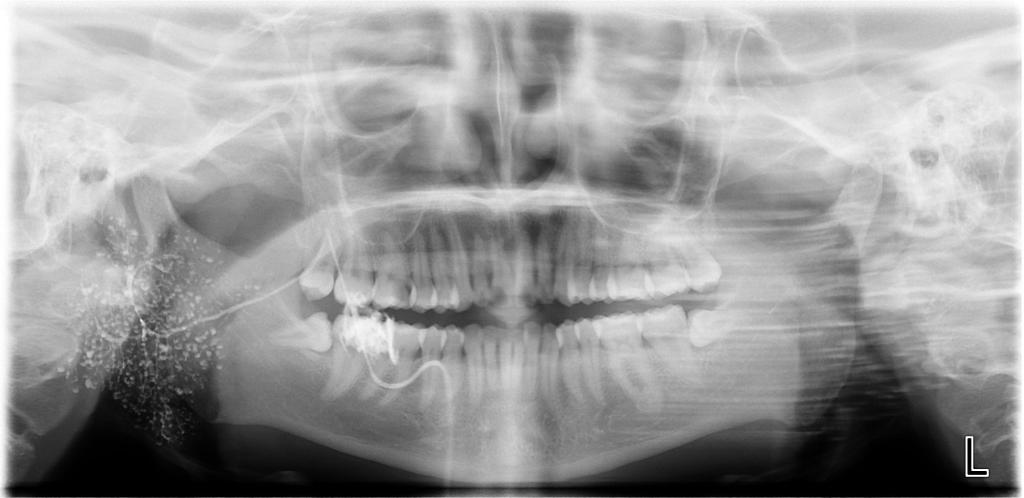

涎腺造影数字化曲面体层片涎腺造影数字化曲面体层片

诊断范围涉及牙体牙髓病、牙周病、阻生牙/多生牙定位、种植牙术前CT评估分析、颞下颌关节CT诊断分析、,颌骨及涎腺疾病、颌面发育畸形、正畸治疗辅助诊断等大部分颌面部疾病,为临床医疗提供强有力的支持。